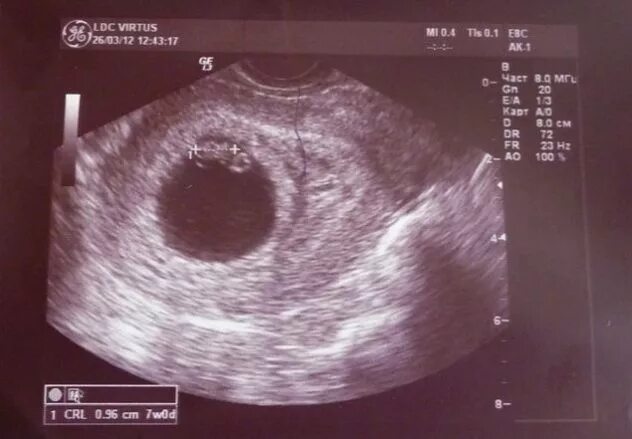

Коричневая мазня при беременности на ранних сроках беременности.7 недель после узи выделения. выделения при беременности 7 недель. выделения на 7 неделе беременности. выделения по неделям беременности.Коричневые выделения при беременности. коричневая мазня на 6 неделе. светло коричневые выделения на 6 неделе.7 недель беременности фото плода на узи. узи на 7-8 акушерской неделе беременности. фото эмбриона в 7 недель беременности фото узи. узи 7 недель беременности узи.Коричневая мазня на 7 неделе. коричневая мазня на 6 неделе беременности. коричневые выделения на 7 акушерской неделе.Коричневые выделения на 6 неделе беременности. выделения на 6 акушерской неделе. коричневые выделения 13 акушерская неделя беременности. 7 недель мажется коричневым.Выделения на 6 акушерской неделе. выделения на 6-7 неделе беременности норма. коричневые выделения на 6 неделе. коричневые выделения на 7 неделе.Узи беременности на ранних сроках. замершая беременность узи. беременность на узи до задержки. узи замершей беременности на ранних сроках.Узи на 7 акушерской неделе беременности. 7 неделя беременности акушерская узи узи. узи 7 недель беременности акушерская фото плода. плод на 7 неделе беременности узи.Эмбрион на 7 акушерской неделе. плод 7 недель беременности размер плода. эмбрион 6-7 недель как выглядит. размер ребенка в 7 недель.Признаки ретрохориальной гематомы при беременности 6-7 недель. узи беременности на ранних сроках.Беременность на ранних сроках. выкидыш по срокам беременности.Мазня на пятой акушерской неделе. коричневые выделения на 7 акушерской неделе. узи 7-8 недель беременности. беременность на ранних сроках 5 недель.Выделения срок 7 недельРетрохориальная гематома на 7 неделе беременности. узи 7 недель беременности гематома. гематома при беременности на ранних сроках. ретрохориальная гематома на узи.Размер ребенка на 7 неделе беременности. размер эмбриона на 7 неделе. плод 7 недель беременности размер плода.При беременности на ранних сроках. мазня при беременности до задержки. беременность выделения до задержки. выделения при беременности на ранних сроках после задержки.Плодное яйцо 6 недель по узи. плодное яйцо 7 недель узи. плодное яйцо 5 недель на узи беременность 6.Коричневатые выделения при беременности. слизистые коричневатые выделения при беременности. коричневатые выделения на ранних сроках беременности. темные коричневые выделения.Выделения срок 7 недельВыделения срок 7 недельЗаключение узи 7 недель беременности. 6 недель беременности по узи. узи беременности 4-6 недель. эмбриональный срок 5 недель узи.Выделения срок 7 недельКоричневые выделениепри беременности. мажущие коричневые выделения. светло коричневая мазня.Коричневатые выделения. светло коричневые выделения. светло желтые выделения.Узи на 2-4 недели беременности. узи беременности на ранних сроках. узи по беременности на ранних сроках.Светло бежевые выделения. желто бежевые выделения. светло розоватые выделения.Розово бежевые выделения. бледно розовые выделения на ранних сроках. бежево розовые выделения при беременности.Выкидыш на ранних сроках беременности. выкидыш на 6 неделе беременности. зародыш на 4 неделе выкидыш.Ведетентя при беременности. бледно коричневые выделения.Выделения на 5 неделе беременности. кровотечение на 5 неделе беременности. кровомазание на 6 неделе беременности. кровит на раннем сроке беременности.Выделения срок 7 недельКоричневатые выделения. выделения прибеременосьи. светло бежевые выделения.Выделения срок 7 недельИмплантационное кровотечение. мажущие кровянистые выделения. кровянистые розовые выделения.Светло коричневая мазня. светло бежевые выделения. небольшие розовые выделения.Темнокорияневве выделения. темно коричневые выделения. темные коричневые выделения.Узи 7 недель беременности гематома. гематома на узи при беременности. ретрохориальная гематома узи заключение.Выделения срок 7 недельРозово бежевые выделения. светло бежевые выделения. выделения розового цвета.